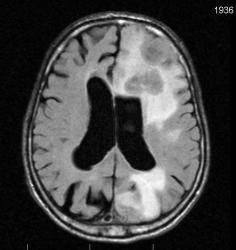

Мужчина 73 лет. За последний год похудел, потерял аппетит. Последний месяц стал плохо ходить, несколько раз падал, неделю назад стал психически не совсем адекватен. Врач - друг семьи, приехавший в гости, настоял на проведении МРТ головного мозга, рентгенографии ОГК и УЗИ брюшной полости. МРТ проводилось в медикаментозном сне, с реанимационным набором наизготовку, по немного укороченным программам. Все закончилось благополучно. Ничего сложного в плане диагностики. Просто не всегда бывает так много и ярко. Есть небольшое продолжение. Потом.

FLAIR:

метастазы